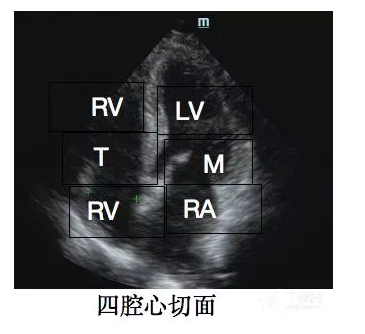

心尖四腔心切面

LV:左室;RV:右室;RA:右房;M:二尖瓣;T:三尖瓣

二尖瓣当二尖瓣瓣口出现

烟雾状回声时,要考虑该处血流瘀滞、血液处于高凝状态。

LV:左室;RV:右室;RA:右房;M:二尖瓣;T:三尖瓣

二尖瓣当二尖瓣瓣口出现

烟雾状回声时,要考虑该处血流瘀滞、血液处于高凝状态。

三尖瓣注意有无三尖瓣下移畸形。

三尖瓣注意有无三尖瓣下移畸形。

室壁观察室壁形态及运动情况。

房间隔当存在

室壁观察室壁形态及运动情况。